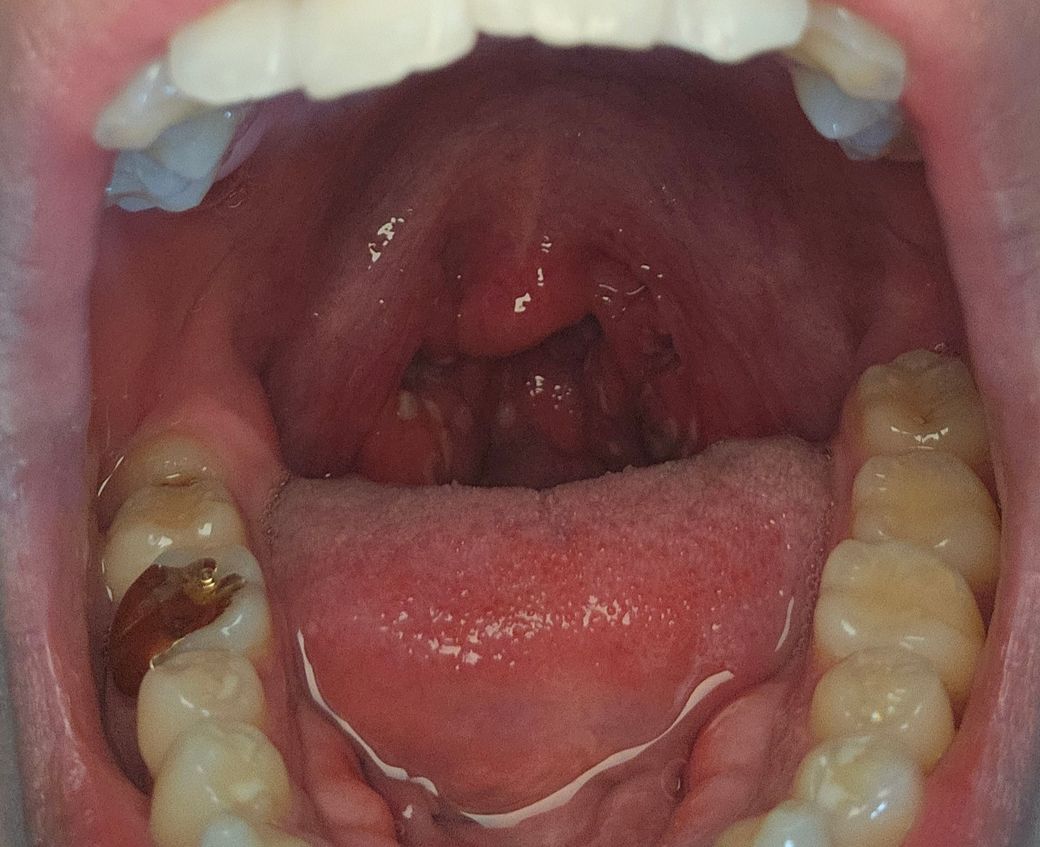

목감기인 줄 알고 약 처방 받았는데 낫지도 않고 어느 순간 편도에 뭐가 나있더라구요 이게 편도결석 편도염 그런건가요? 목 찢어질거같네요.. 3,4일간 열과 몸살도 같이 나고 그럽니다

편도 결석보다는 편도염이 심한 상태라고 판단됩니다. 하얗게 보이는 부분은 염증이 심해서 나타난 소견 같아요. 암은 아니구요. 일단 편도염 약을 당분간 복용하면서 증상 조절해 보시기 바랍니다.